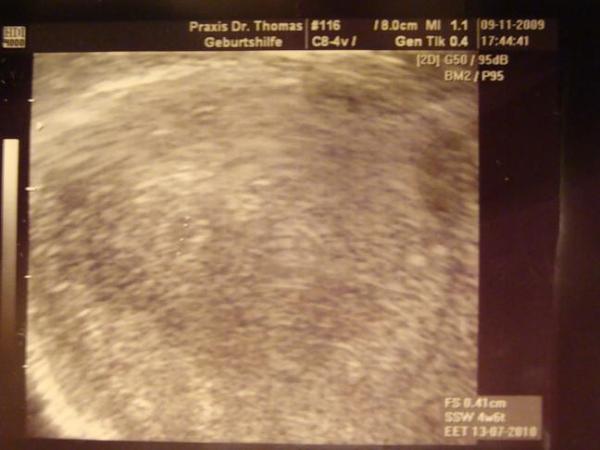

nach dem hier einige schon was zu sehen hatten auf ihren us hab ich etwas angst das was nicht in ordnung ist , ich bin so ängslich in der ss das ist schon schlimm . ich häng euch mal ein bild ran

Bild zu etwas angst - Forum für Juli - Mamis

Das Bild sieht doch gut aus. Dein FA hat vor 2 Tagen eine Fruchthöhle markiert, die 41 mm groß war. Passt doch alles perfekt. Aus einem anderen Winkel wäre die FH vielleicht etwas deutlicher zu sehen gewesen. LG Mareike

Man kann die Fruchthöle doch schon erkennen. Das ist doch super für die fünfte Woche. Nächstes Mal siehst du mehr.